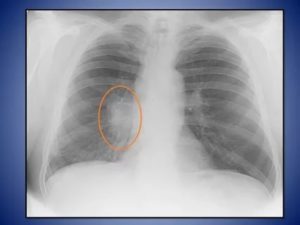

Опасной, но, к счастью, нечасто встречающейся причиной того, что корни легких уплотнены и расширены, является онкологический процесс в бронхах и органах средостения. Такой процесс, как правило, односторонний, поэтому изменение корня легкого наблюдается только с одной стороны.

После проведения обзорной рентгенографии грудной полости в двух проекциях врач-рентгенолог ставит заключение: «Корни легких уплотнены и малоструктурны».

Нарушение структуры корня легкого, то есть невозможность отличить сосуд от бронха, появление затемнения на корне, обычно встречается при первичном туберкулезе, онкологических процессах.

На рентгенограмме при обширном туберкулезе или центральном раке легкого вместо корня может визуализироваться тень различных контуров, представляющая собой очаг (до 10 мм диаметром) или инфильтрат (более 10 мм).